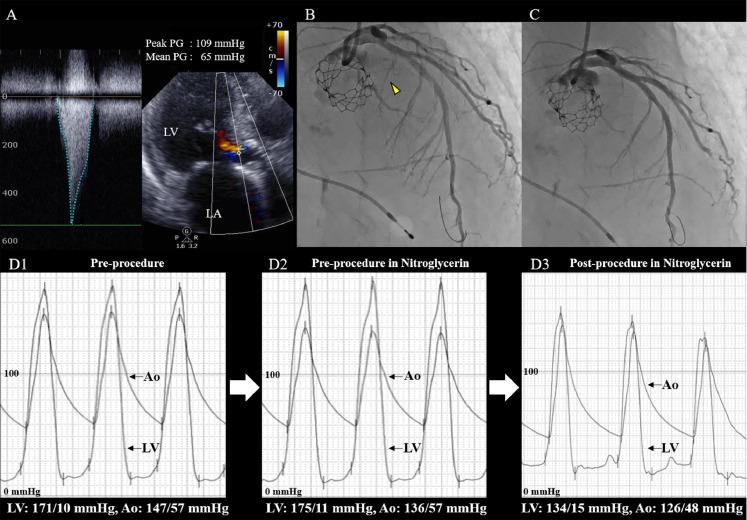

Acute decompensated heart failure (ADHF) due to severe aortic stenosis (AS) and concomitant left ventricular outflow tract (LVOT) obstruction is a serious condition. Treatment with medication alone is sometimes difficult, and the efficacy of further interventional strategies has not been fully elucidated. In patients with high surgical risks, combination therapy using transcatheter aortic valve replacement (TAVR) and percutaneous alcohol septal ablation (ASA) is used as a non-surgical intervention. However, this treatment cannot be performed under unstable hemodynamic conditions. This report highlights the utility and efficacy of emergent balloon aortic valvuloplasty (BAV) in controlling heart failure and its potential to serve as a bridge to curative therapy, even in older patients with ADHF due to severe AS with concomitant LVOT obstruction. Furthermore, combination therapy with TAVR and percutaneous ASA could be safely performed after controlling for ADHF using BAV. Non-surgical management is a more feasible treatment option in older patients with ADHF who are at higher risk of complications during surgical intervention. < Management of acute decompensated heart failure (ADHF) due to severe aortic stenosis (AS) and concomitant left ventricular outflow tract (LVOT) obstruction can be difficult. Despite concomitant LVOT obstruction, emergent balloon aortic valvuloplasty is potentially useful and effective for controlling heart failure and could become a bridge to subsequent combination therapy using transcatheter aortic valve replacement and percutaneous alcohol septal ablation. This sequential non-surgical management is a novel strategy for older patients with high surgical risk and ADHF due to severe AS with concomitant LVOT obstruction.>.